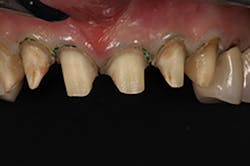

The milled provisionals were removed from the sprues and polished (figure 6). At the first clinical visit, the teeth were prepared and retraction cord placed to expose the crown margins (figure 7). Note that neither lateral incisor was exposed during tooth preparation.

Figure 7: At the first clinical visit, the teeth were prepared and retraction cord was placed to expose the crown margins.